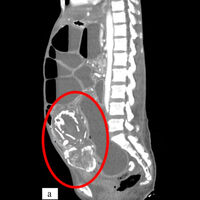

Врачи из Медицинского университета SUNY Upstate рассказали о случае смерти женщины из Конго из-за тяжелого голода, вызванного сдавлением тонкой кишки окаменевшим плодом ребенка, который она носила в своем теле около девяти лет. О случае сообщает Daily Mail.

Женщина родом из Конго обратилась к врачам в Нью-Йорке с жалобами на спазмы желудка. Сканирование обнаружило в теле 50-летней женщины литопедиона —«каменного ребенка», представляющего собой кальцифицированный плод.

В молодости женщина дважды была вынуждена покинуть родные места, сначала переехав из Конго в Бурунди, а затем в Танзанию из-за конфликтов. В Танзании она обосновалась и родила восьмерых детей естественным путем. Трое умерли вскоре после родов. Во время своей девятой беременности она посетила клинику в лагере беженцев, заметив на 28 неделе беременности, что ее ребенок больше не двигается.

Медики сказали ей, что у ребенка нет сердцебиения, и порекомендовали ей вернуться через две недели, если организм не избавится от плода сам. Однажды снаружи клиники ее встретили люди, обвинявшие ее в убийстве ребенка. Это привело к тому, что мать решила больше не обращаться за медицинской помощью. Затем она носила мертвый плод в течение девяти лет и не контактировала с медиками.